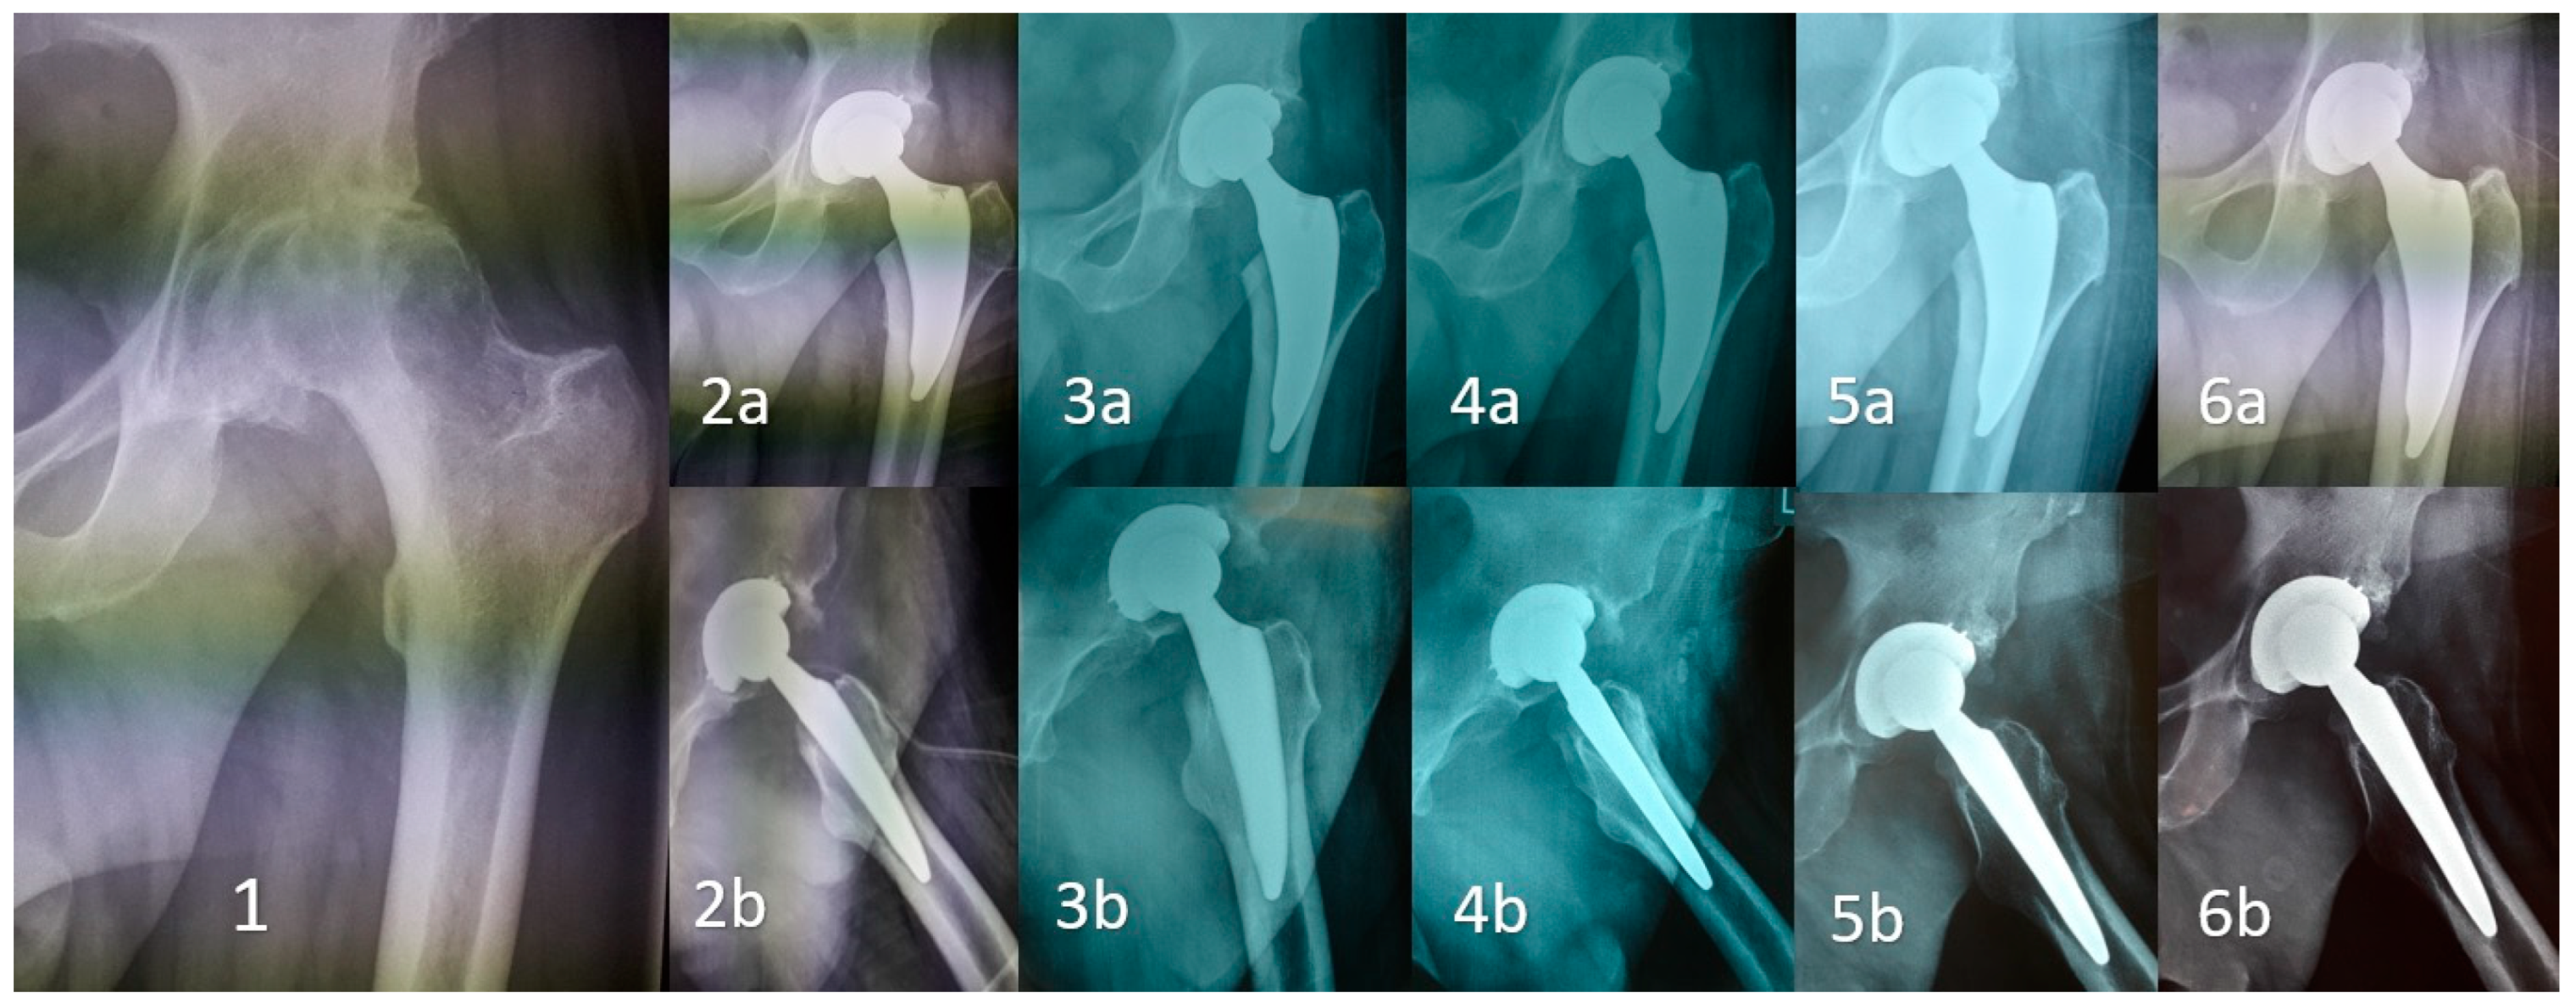

Early Clinical and Radiographic Outcomes of Total Hip Arthroplasty with DELTA ST-C Cup and MINIMA S Stem

1. Introduction

2. Methods